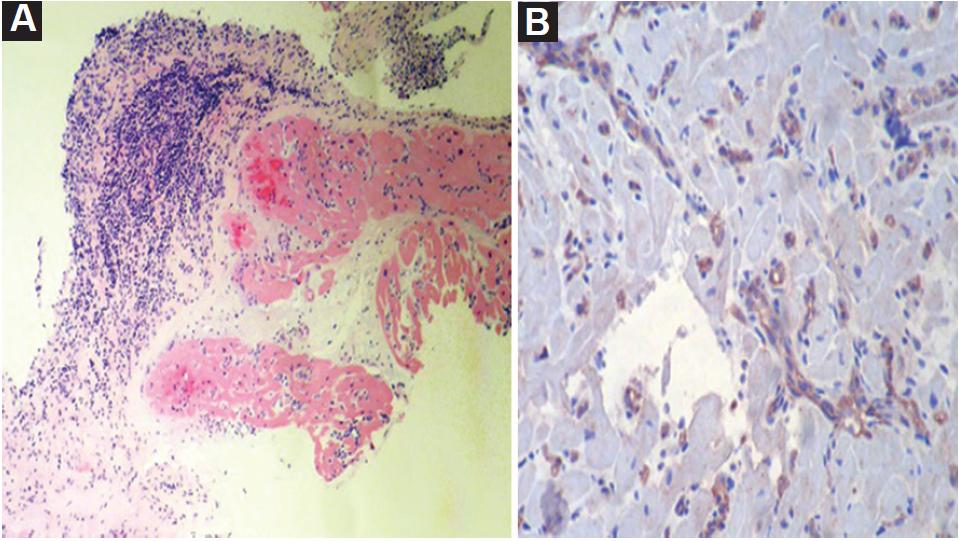

A 31-year-old male started 1 day before admission with pain in the upper right limb, dizziness, nausea, diaphoresis, and paleness followed by loss of postural tone and loss of consciousness 3 min long. He denied previous similar episodes, fever, diarrhea, chest pain, or head trauma. The patient's vital signs, neurological and cardiovascular examinations on admission were normal. The patient history was notable for HT because of dilated cardiomyopathy 6 years before the current even. Immunosuppressive therapies at the time of presentation included cyclosporine, mycophenolate, and prednisolone without recent changes. The patient denied taking herbal supplements. A differential cell count, leukocytes, hemoglobin, blood glucose, and electrolyte levels were normal, with cyclosporine levels in subtherapeutic range (122.8 ng/mL). An electrocardiogram (ECG) showed sinus rhythm, with a pattern of right bundle branch block, with a QT interval of 420 ms and a QTc interval by Bazzet's formula of 530 ms. R-R distance was 0.64 s (Fig. 1A) that had not been documented on his follow-up ECG in the outpatient heart transplant consultation. His transthoracic echocardiogram (TTE) documented severe left ventricular dysfunction (left ventricle ejection fraction [LVEF]: 20%), with generalized hypokinesia, right ventricle of normal size but with systolic dysfunction (tricuspid annular plane systolic excursion [TAPSE] 10 mm and peak systolic velocity of tricuspid annulus color tissue Doppler 4 cm/s) and global longitudinal strain (GLS) was −5.5%. The right heart catheterization document increased pressures (central venous pressure 18 mmHg, wedge 27 mmHg, and mean pulmonary arterial pressure of 30 mmHg) and coronary angiography without vasculopathy. Endomyocardial biopsy (EMB) (Fig. 2) revealed acute humoral and cellular rejection (Grade 3R ISHLT). The specific donor antibody was positive against HLA Class II DRB *1.

Figure 2 Endomyocardial biopsy: A. Extensive interstitial and perivascular lymphocytic infiltrate, with several foci of myocytic damage. Some capillaries with leukocyte marginalization. B. Immunohistochemistry for C4d: focal positivity in approximately 60% of capillaries: Grade 3R ISHLT.

With these findings consistent with an acute rejection of the graft, steroid bolus was initiated as well as consolidation therapy with plasmapheresis for 2 weeks followed by immunoglobulin and subsequent rituximab. The electrocardiographic changes were corrected after completion of plasmapheresis and immunoglobulin management (Fig. 1B; QTc of 424 mseg by Bazett's formula and QT interval of 360 mseg, heart rate: 83 bpm), with resolution of symptoms. His TTE showed a LVEF 55% without segmental contractility disorders, with recovery of the right ventricular function (TAPSE 21 mm, S´-wave velocity 10 cm/s) and GLS of −6.6%. The control EMB showed focal lymphocytic and 30% CD4 positivity in capillaries (Grade 1R ISHLT), concluding improvement with the management to a mild rejection. He was discharged home with an immunosuppression management adjustment as the cause of rejection was considered to be related to subtherapeutic levels of cyclosporine.